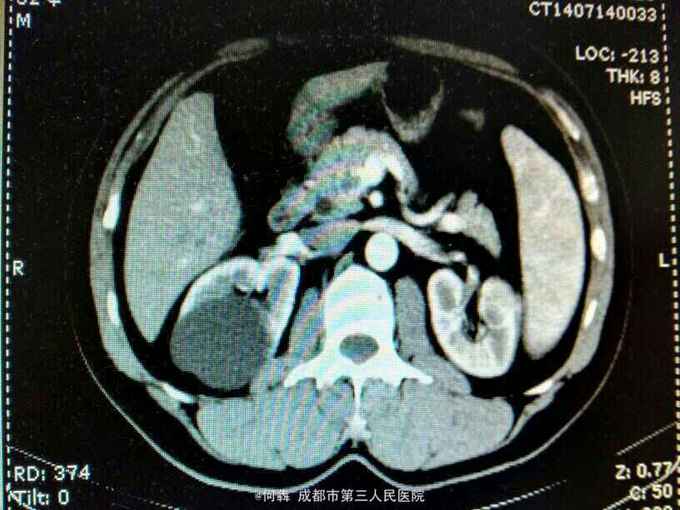

53岁,男性,因“腹腔镜下双肾囊肿切除术后1年余,左腰部窦道形成10月余”入院。无高血压病及糖尿病。

左腰部窦道形成伴少许脓液。窦道脓液培养出绿脓杆菌。

腹腔镜双肾囊肿切除术后窦道形成伴感染。现使用敏感抗生素派拉西林舒巴坦抗感染。